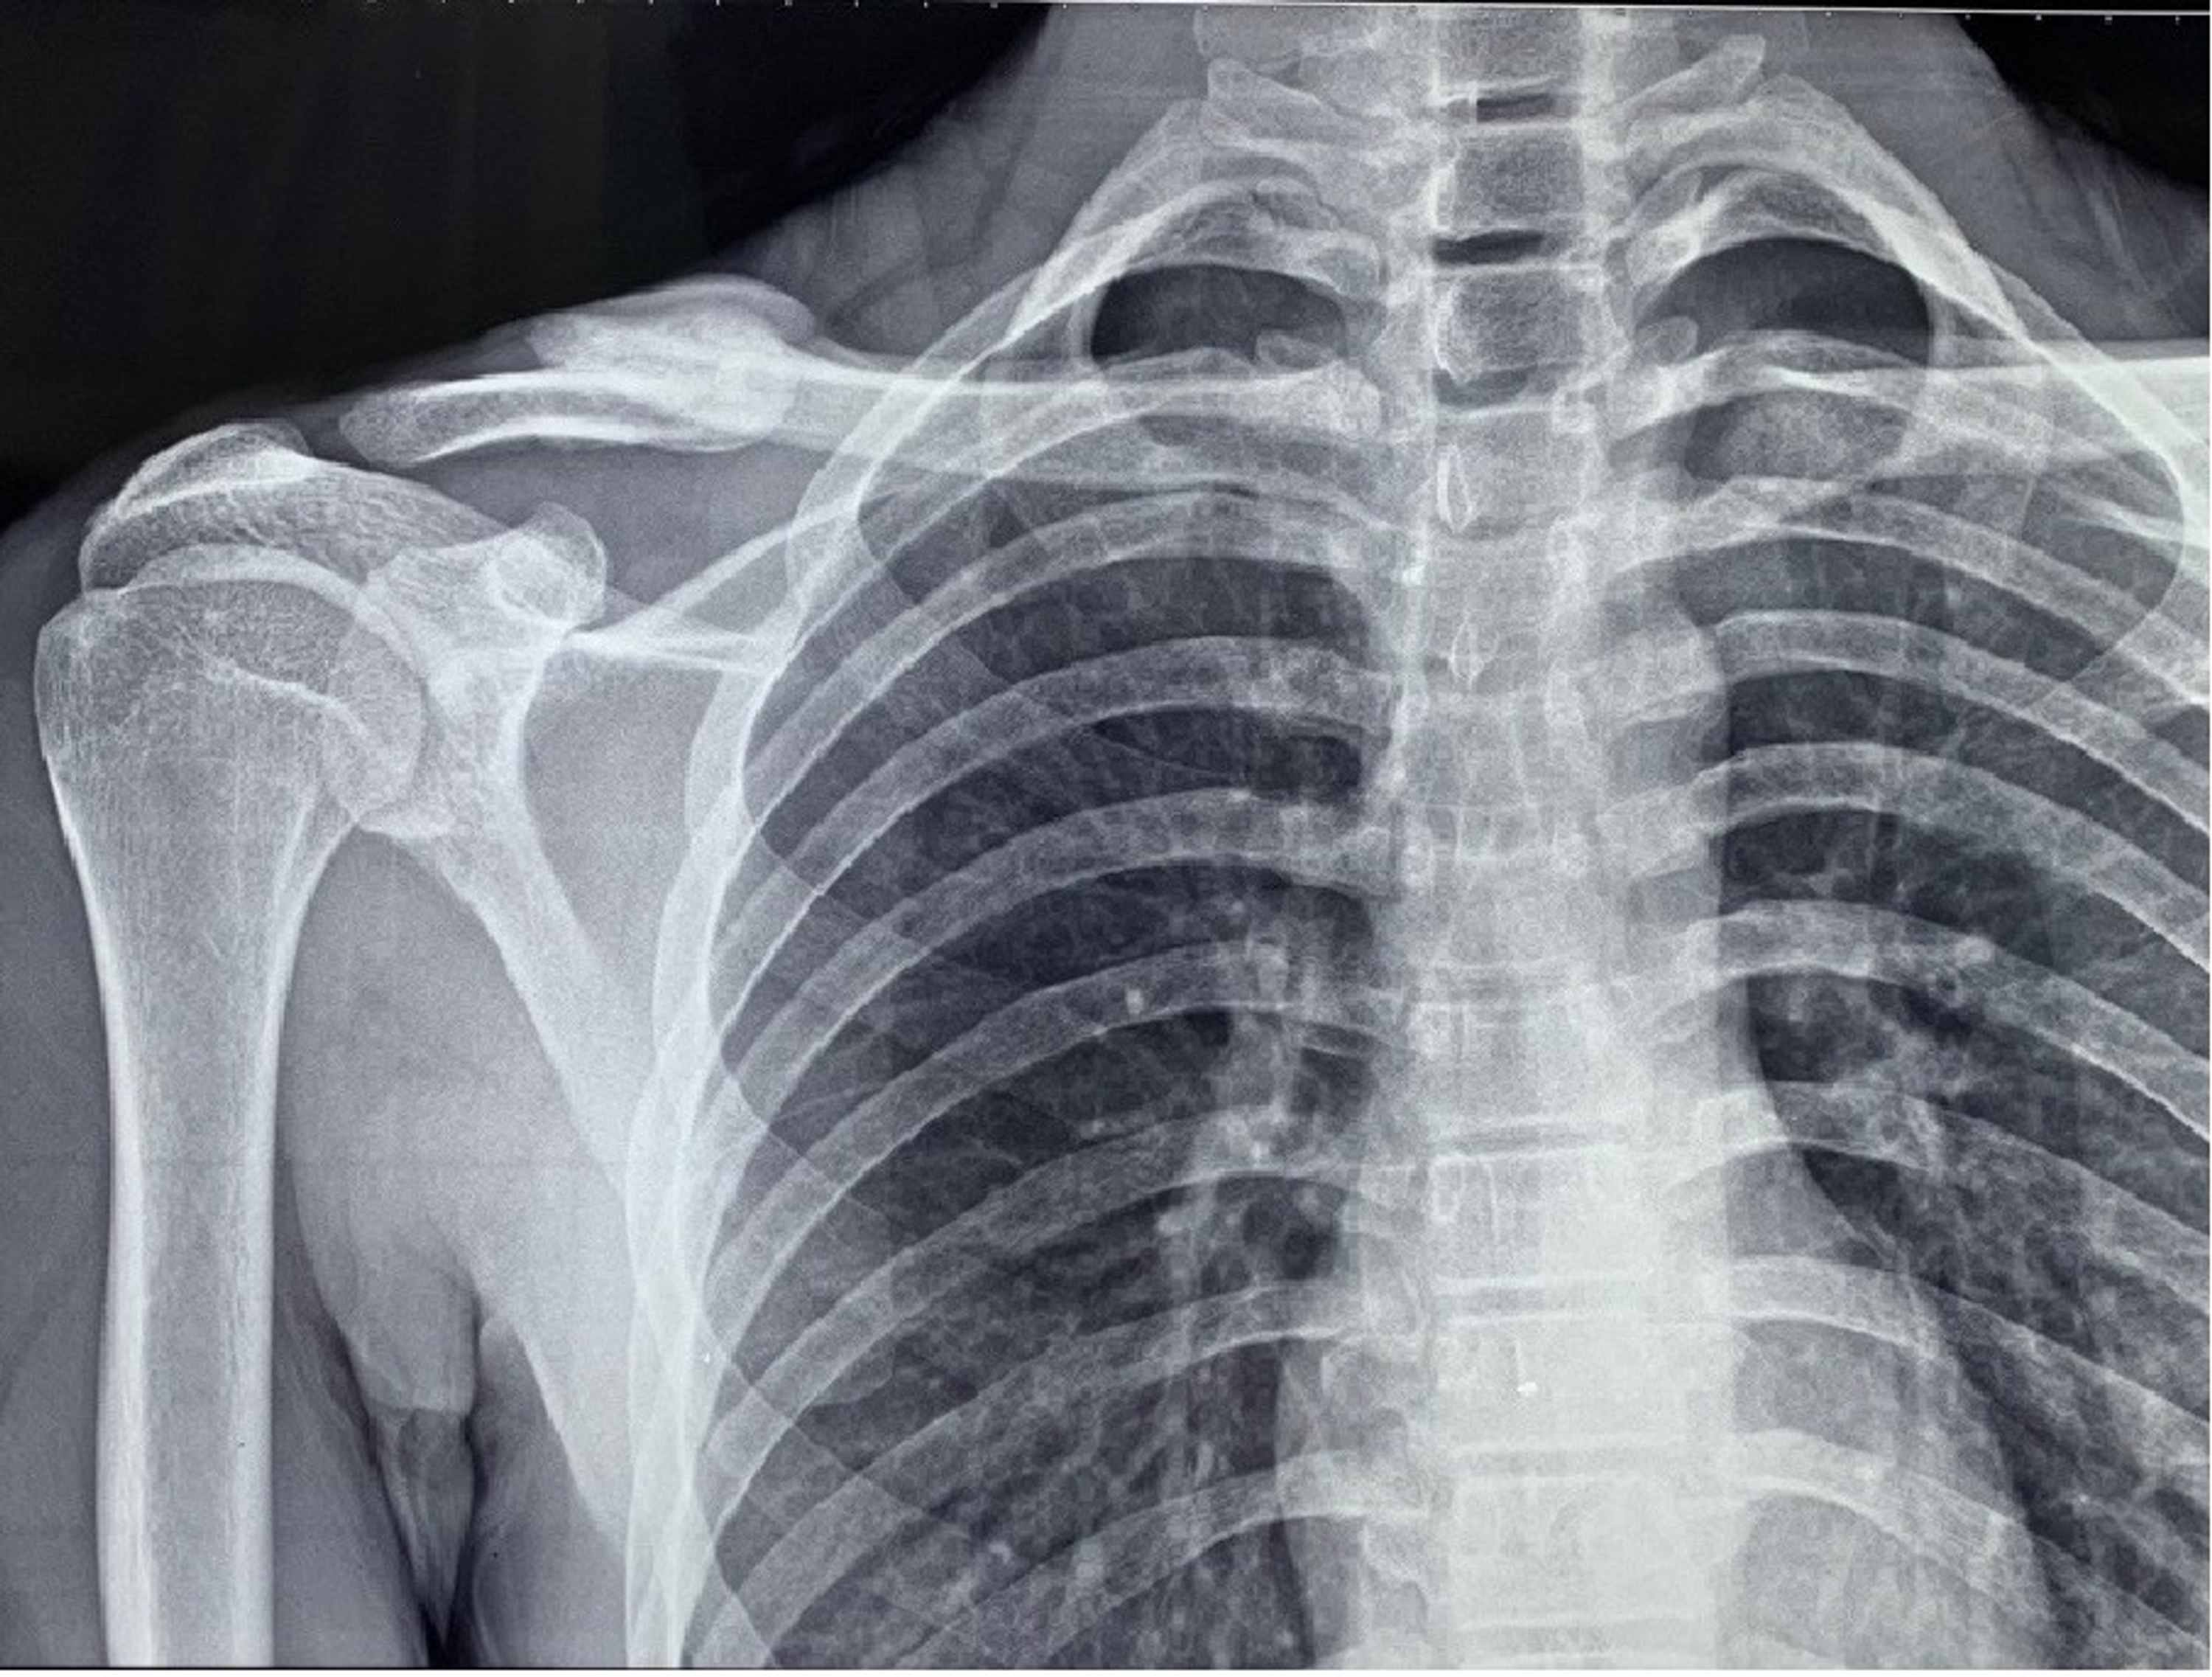

Beach Chair Position Clavicle Surgery And Children. Upright x-rays of the patient will help to determine the true displacement and shortening of the fracture. Techniques in Shoulder and Elbow Surgery.